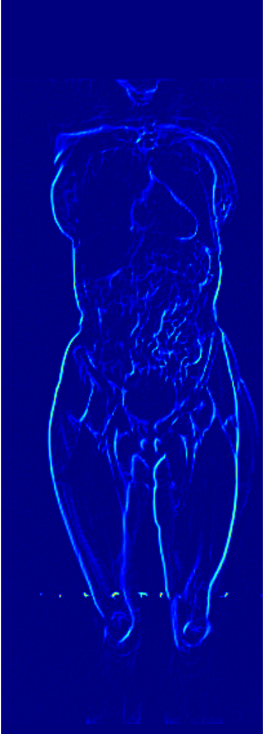

Recently, the use of diffusion-based models for image inverse problems has shown great success [63, 18, 35, 51, 40, 52]. This motivated our X-Diffusion to investigate learning volumes instead of images. In this light, our X-Diffusion proposes a novel architecture to allow learning on 3D volumetric data by view-dependent cross-sections. This allows for full MRI generation with unprecedented accuracy from a single MRI slice, multiple slices, or even from DXA image if paired data is available (see Figure 1). To the best of our knowledge, X-Diffusion is the first work to successfully generate detailed MRI volumes from a single DXA scan, bridging the gap between two common data modalities in medical imaging. It is important to note that the generated MRIs are not clinical replacements for true MRIs, but could provide a quick, affordable, and informative “pseudo-MRI" before conducting a full MRI examination.

3.4 DXA to MRI Volume Generation

DXA is a single image data modality that is similar to X-ray but includes other non-bony information such as tissue mass [67]. It measures bone mineral density and body fat composition. The radiation level is low enough that it is acceptable for conducting studies of healthy participants, such as the UK Biobank. In order to leverage X-Diffusion to synthesize the MRI volume from a single DXA (as in Figure 3), they have to be aligned, and registered. Note that, the size of the DXA does not match the MRI () and the scans are not registered. The two modalities in UK BioBank were not taken simultaneously but close in time hence why we believe registration is feasible for these two sequences as illustrated extensively in [79].

In order to tackle this domain gap, we leverage a registration network [79] paired with a X-Diffusion to achieve DXA to MRI slice generation. [79] introduced a multi-modal image-matching contrastive framework, that is able to learn correspondences between DXA and middle coronal MRI slices. These networks extrapolate the DXA scan by a transform to the coronal MRI slice by harnessing the embedded patterns and features of the DXA and the coronal MRI mid-slice. X-Diffusion is then trained on the registered DXA () and corresponding MRI slices in () in the target MRI volumes and is able to produce precise MRI volumes that align with the DXA scans (see Figure 5 left). The other details are similar to Section 3.2 and Section 3.3.

Notably, X-Diffusion achieves state-of-the-art dB for a few input slices while baselines require more than 60 input slices to achieve similar performance (Figure 7). The margin is more than 12 dB PSNR for the 1-slice input in both the BRATS and the UK Biobank benchmarks (see Table 1 and Figure 6). For reference, two randomly sampled MRIs from UK Biobank would have a PSNR of 15.95 dB 0.36 (on 4800 randomly sampled examples). Omitting the preprocessing step of alignment DXA to MRI, leads to a drop of PSNR on average by 2.87 dB (29.01 dB 26.14 dB). The slices from 3D reconstructed volumes at varying depths and axis of rotation, visually match the ground truths for both brain and whole-body scans (see Figures 4 and 5 left). We also plot the error map (Figure 3) and the spread of the error (Figure 5 right) of such X-Diffusion generations to highlight the differences with the ground truth MRIs.